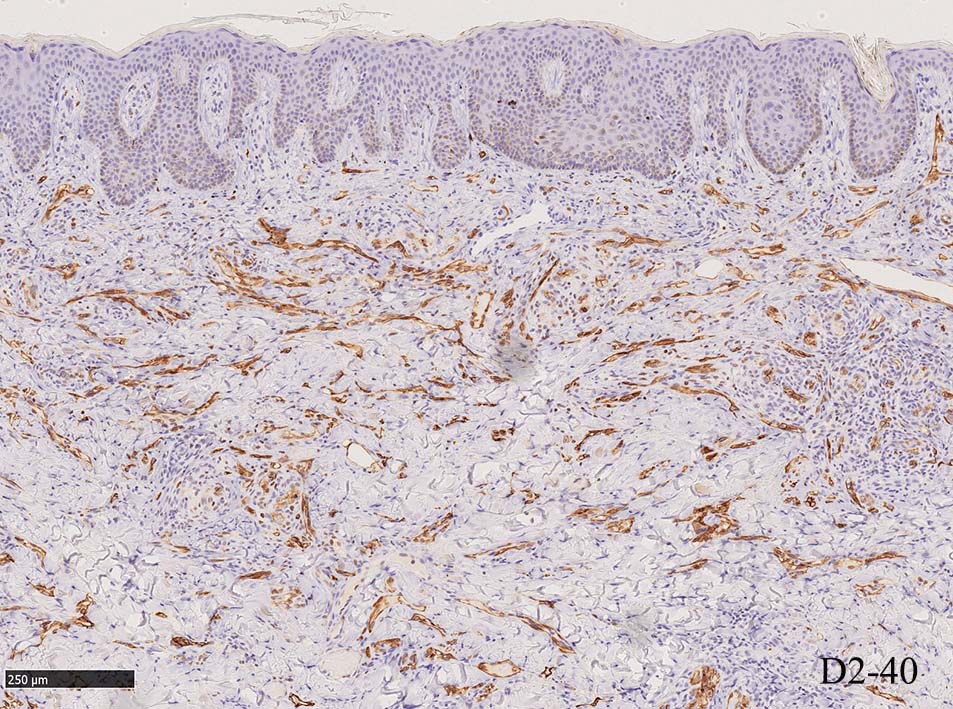

増生細胞はCD31, CD34, Factor Ⅷ, D2-40などが陽性を示す.

細血管周囲に血管内皮様の紡錘形細胞が増生, 一部に赤血球をいれた裂隙の形成がある. 細胞の異型はみられず, mitosisの増多もない. hemosiderin-laden macrophageが散在する.

病変は真皮内に現局している. 初期斑状病変に相当すると考えられる. 本例では, 特徴とされる形質細胞浸潤増加はみられない.